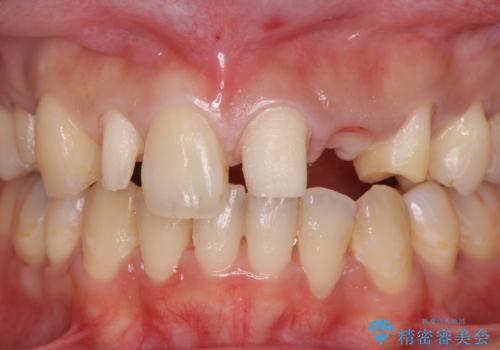

前歯の審美的なブリッジ (歯列矯正後)

- 歯列矯正後に前歯にブリッジを入れた方の経過です。

矯正治療の術前後の経過は以下をご覧ください。

矯正治療で歯の位置を整えてからブリッジを入れると歯の幅を自由に設定できるため、左右対称にできます。結果矯正なしでいきなりセラミックにする場合と異なり、無理に角度を変えたりする必要がなく、神経をなるべく温存したまま審美的なセラミック治療が行えます。